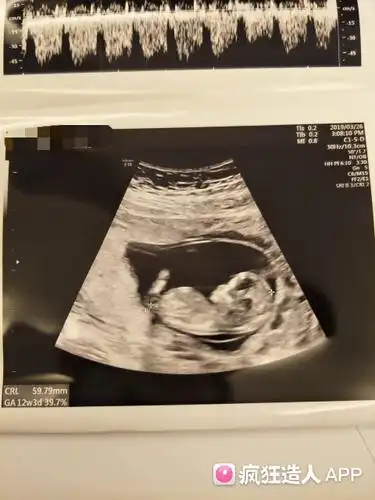

12周3天的nt图看男女,有会看的姐妹帮看看吗